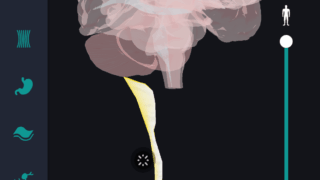

はじめに 本記事では、人体解剖学における専門的な部位の知識を始めに、効果的な勉強法についてご説明します。 人体解剖学では様々な器官や筋肉、骨の名称を覚えるだけではなく、体のどの位置に存在するのかまで覚えなければなりません。そのため、できるだ...